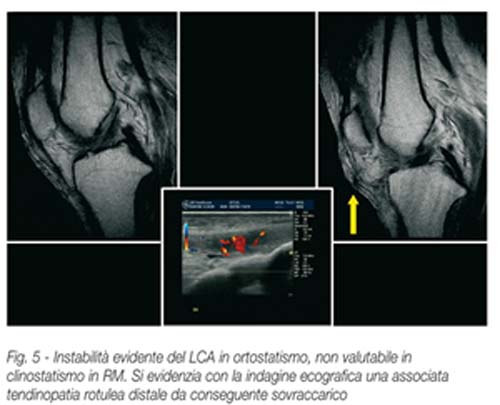

L’esame ortostatico in risonanza magnetica a carico delle componenti legamentose del pivot centrale, consente spesso di porre l’accento su eventuali instabilità non evidenziate all’esame clinostatico.

Altrettanto risulta molto utile nella valutazioni delle disinserzioni meniscali, negli esiti di meniscectomia parziale, laddove sovente il paziente lamenta in carico pseudo blocchi, che all’indagine in clinostatismo non possono essere evidenziati.